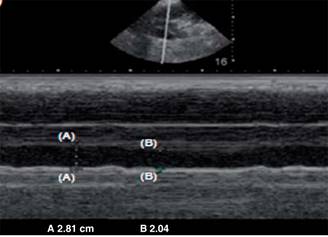

Figura 2: Medición de la colapsabilidad de vena cava inferior en modo M .7

El paciente deberá encontrarse en decúbito dorsal y se localizará la ventana acústica subxifoidea o subcostal al colocar el transductor por debajo y ligeramente hacia la derecha del apéndice xifoides, dirigiendo el transductor hacia el hombro izquierdo del paciente aproximadamente a 15o, con la marca del transductor hacia la izquierda de la persona en sentido horario a las dos o tres y con una profundidad de 16 a 20 cm, con el fin de localizar el corazón para después realizar un giro continuo en sentido antihorario del transductor de las tres a las 12 y ligero desplazamiento hacia la izquierda. Deberán realizarse mediciones del diámetro mayor de un ciclo respiratorio en inspiración y espiración.7

H. ¿Qué es el índice de colapsabilidad de la vena cava inferior? En 2009, se establece la relación matemática del índice de colapsabilidad de la vena cava inferior como la relación matemática que guarda el diámetro mayor y el diámetro menor de la vena cava inferior sobre el diámetro mayor de ésta, expresado en porcentaje en los pacientes con ventilación espontánea durante un ciclo respiratorio, en principio con personas bajo tratamiento sustitutivo de la función renal a expensas de hemodiálisis en 24 pacientes, en las cuales se demostró que la variación de colapsabilidad de la vena cava inferior resultó un marcador confiable de hipovolemia,10 después la utilizan como una medición para predecir la respuesta a la administración de líquidos con un punto de corte de 40% con sensibilidad de 70% y especificidad de 80%.11

Colapsabilidad de la vena cava inferior = (diámetro mayor-diámetro menor/ Diámetro mayor) x 100